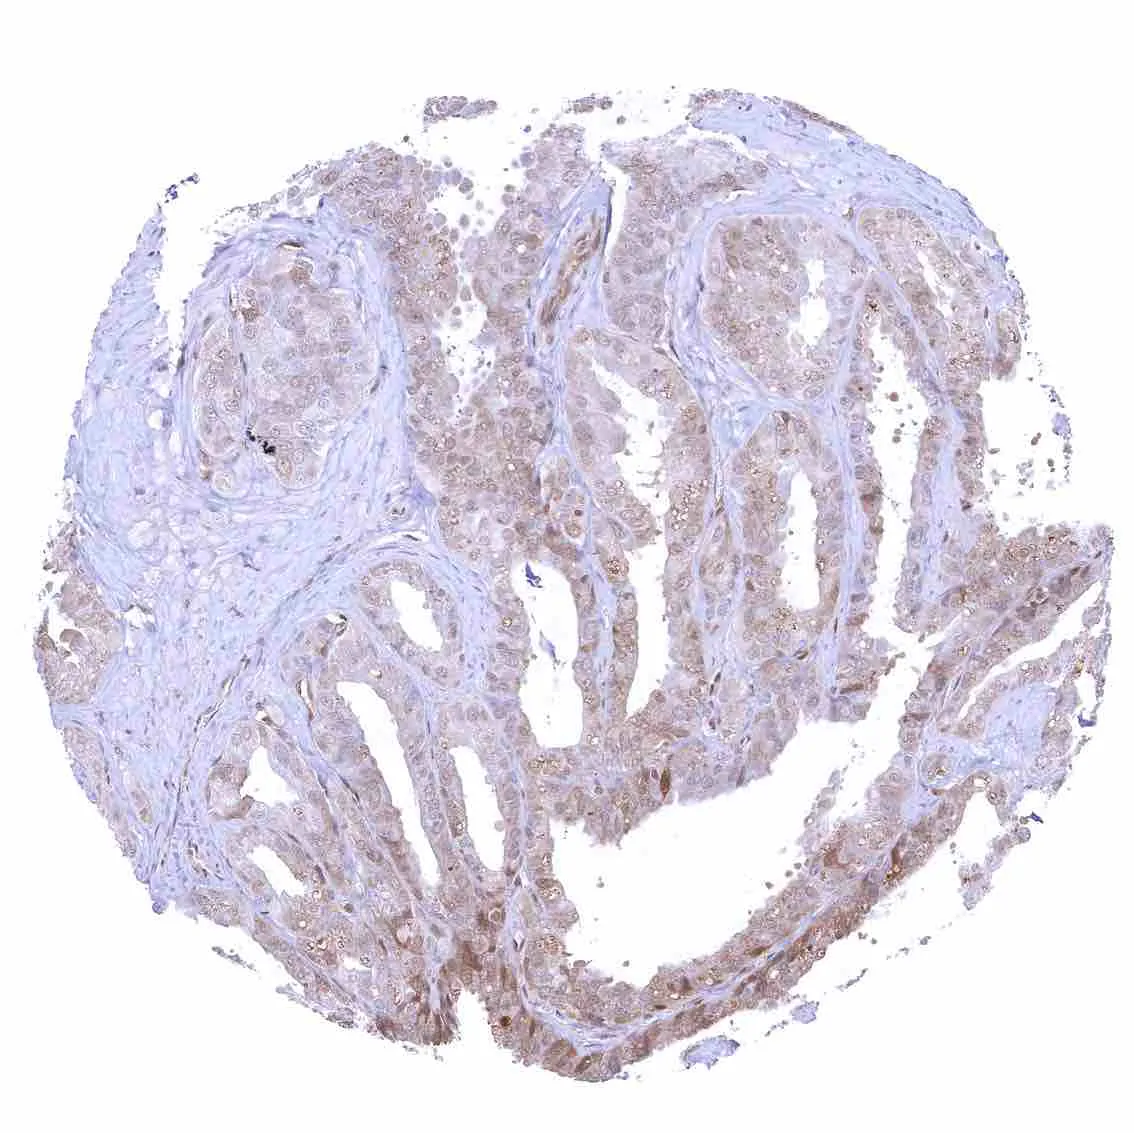

Breast – Moderate to strong nuclear p27 positivity of a large fraction of glandular epithelial cells.